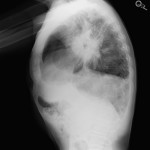

- Lateral CXR

Q 1: This imaging sign is classic for what diagnosis?

- Pulmonary Alveolar Proteinosis – “PAP”

- Usual Interstitial Pneumonia – “UIP”

- Sarcoidosis

- Mycobacterium Tuberculosis

Q 2: If this is the so called “Donut Sign” – what anatomic structure is the hole in the donut?

- Trachea

- Right Upper Lobe Bronchus

- Left Upper Lobe Bronchus

- Left Lower Lobe Bronchus

- Bronchus Intermedius